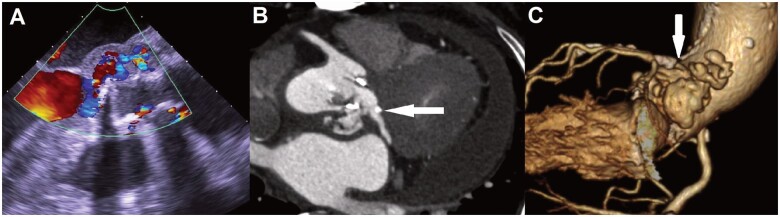

人工瓣膜心内膜炎,尤其是并发主动脉根部脓肿和左心室流出道破裂时,是一种危及生命的疾病。我们介绍了一例感染性人工主动脉瓣膜心内膜炎合并左心室流出道破裂的病例,该病例通过根部手术成功治愈,手术中使用了安全吻合器重建受损的主动脉瓣环。

Prosthetic valve endocarditis, especially when complicated by an aortic root abscess and a left ventricular outflow tract rupture, is a life-threatening condition. We present a case of infective prosthetic aortic valve endocarditis with a ruptured left ventricular outflow tract successfully treated with a root-commando operation using a secure anastomosis for reconstruction of the damaged aortic annulus.